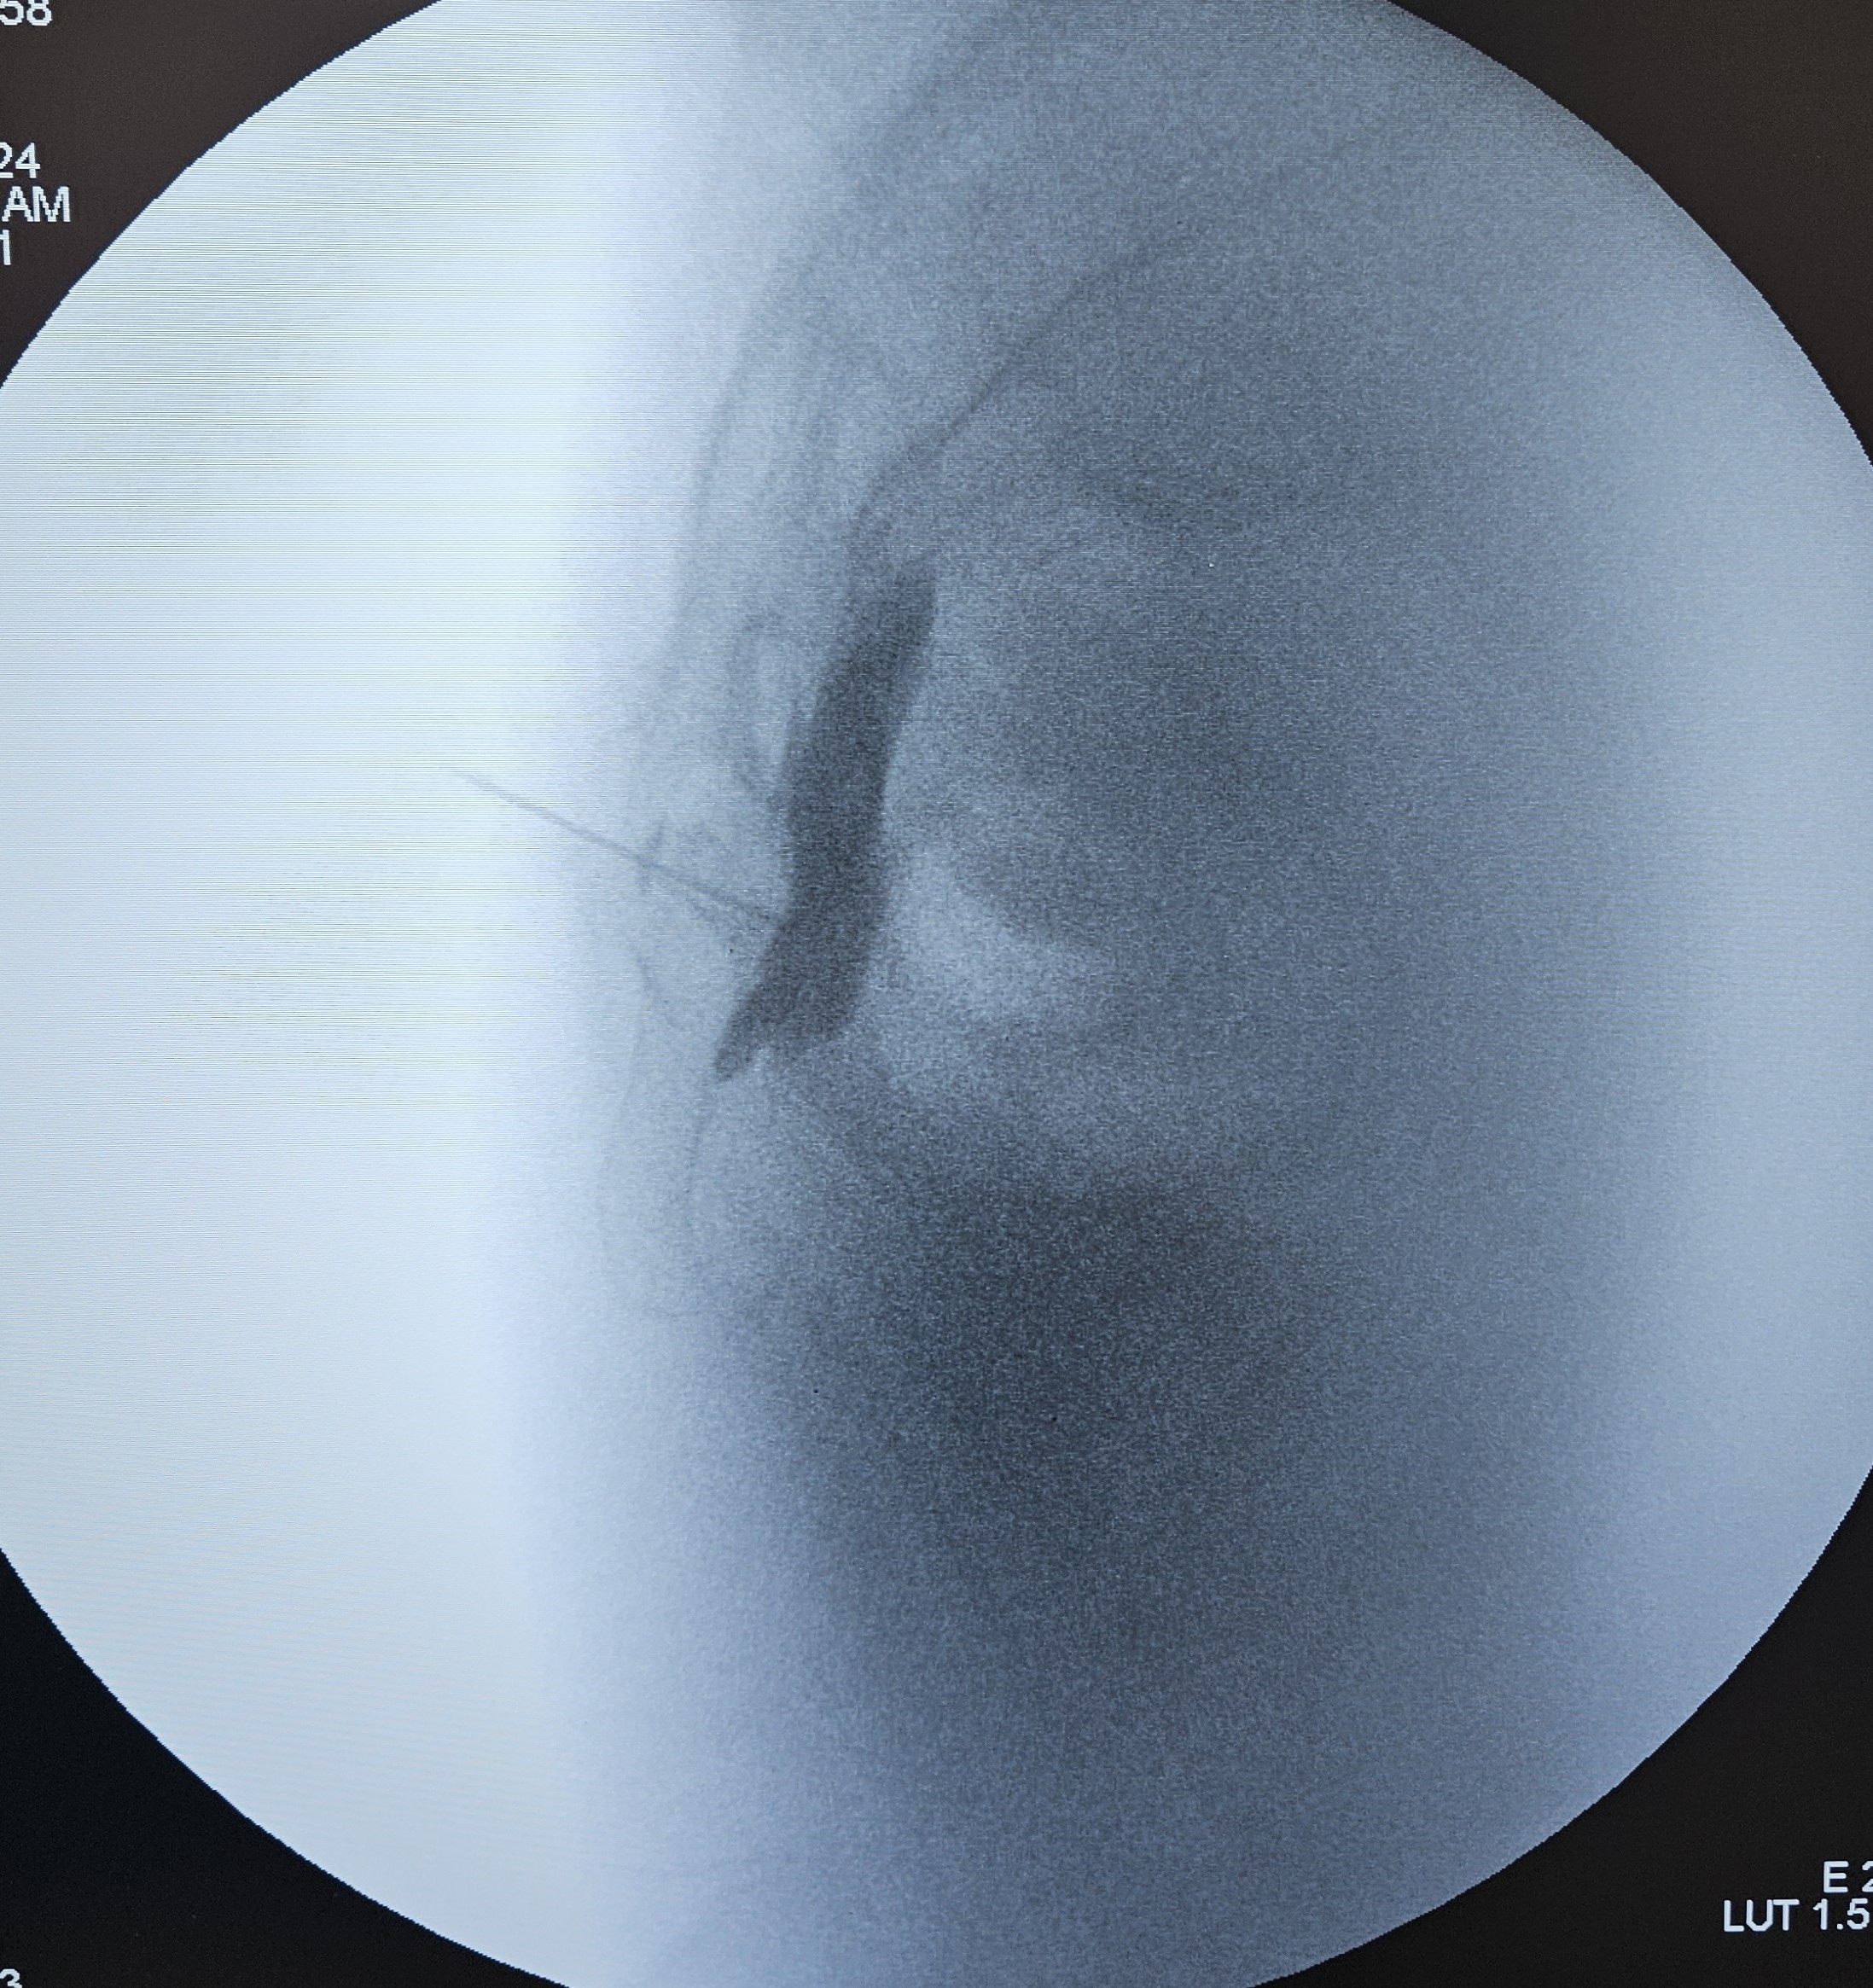

Με τον ασθενή σε πρηνή θέση και υπό τοπική αναισθησία και ακτινοσκοπική καθοδήγηση, εισάγεται μια λεπτή βελόνα, η οποία διαπερνά τον ιεροκοκκυγικό σύνδεσμο και μέσω άρθρωσης προωθείται ακριβώς κάτω από τον κόκκυγα, όπου βρίσκεται το γάγγλιο. Ακριβώς μπροστά από το γάγγλιο εδράζεται το ορθό, όποτε απαιτείται ιδιαίτερη προσοχή στην προώθηση της βελόνας για να αποφευχθεί η τυχόν τρώση του ορθού.

Μετά τη σωστή τοποθέτηση της βελόνας , εγχύεται σκιαγραφική ουσία για την απεικόνιση του γαγγλίου και αμέσως μετά τοπικό αναισθητικό και στεροειδές.